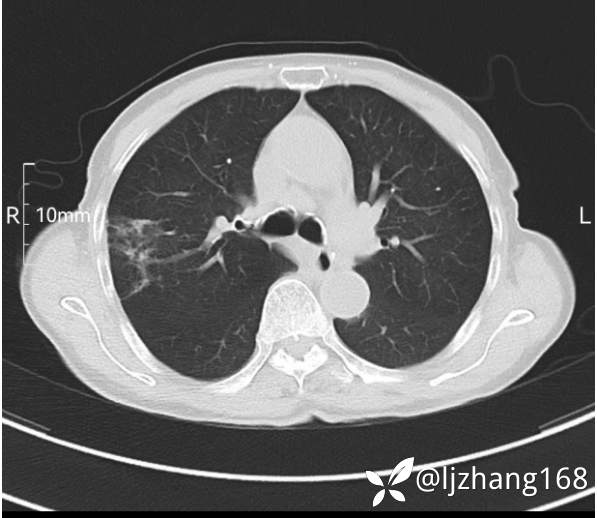

74岁女患,反复咳嗽2月,右肺空洞性病变,炎症OR肿瘤(有病理)

简要病史:2月前开始受凉后出现咳嗽,咳少许白色粘液痰,痰不易咳出,无痰中带血及咯血,无畏寒发热,外院胸部CT提示右下肺空洞病变,脓肿可能性大,常规抗感染治疗效果不佳。既往否认“糖尿病”等病史,有高血压基础病史,无吸烟史。

辅助检查:胸部CT右肺下叶前基底段结节并空洞

临床诊断:右肺空洞:脓肿?